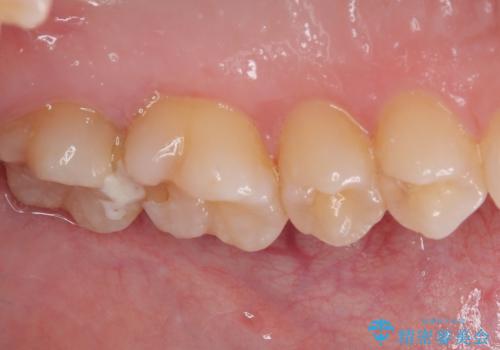

奥歯2歯の間からむし歯が広がったようで、最後方歯は既に神経が失活している状態で、手前の歯は神経組織に問題はないものの速やかに処置が必要な状態でした。

最後方歯は根管治療を行った上でオールセラミッククラウンにて補綴治療を行うこととし、手前の歯はセラミックインレーにて修復治療を行うこととしました。

当院に来院された時には既に痛みはなく、治療終了までスムーズに進めることができました。

今後は定期的にレントゲン写真を撮りながら、根管治療の経過観察を行っていくことになります。